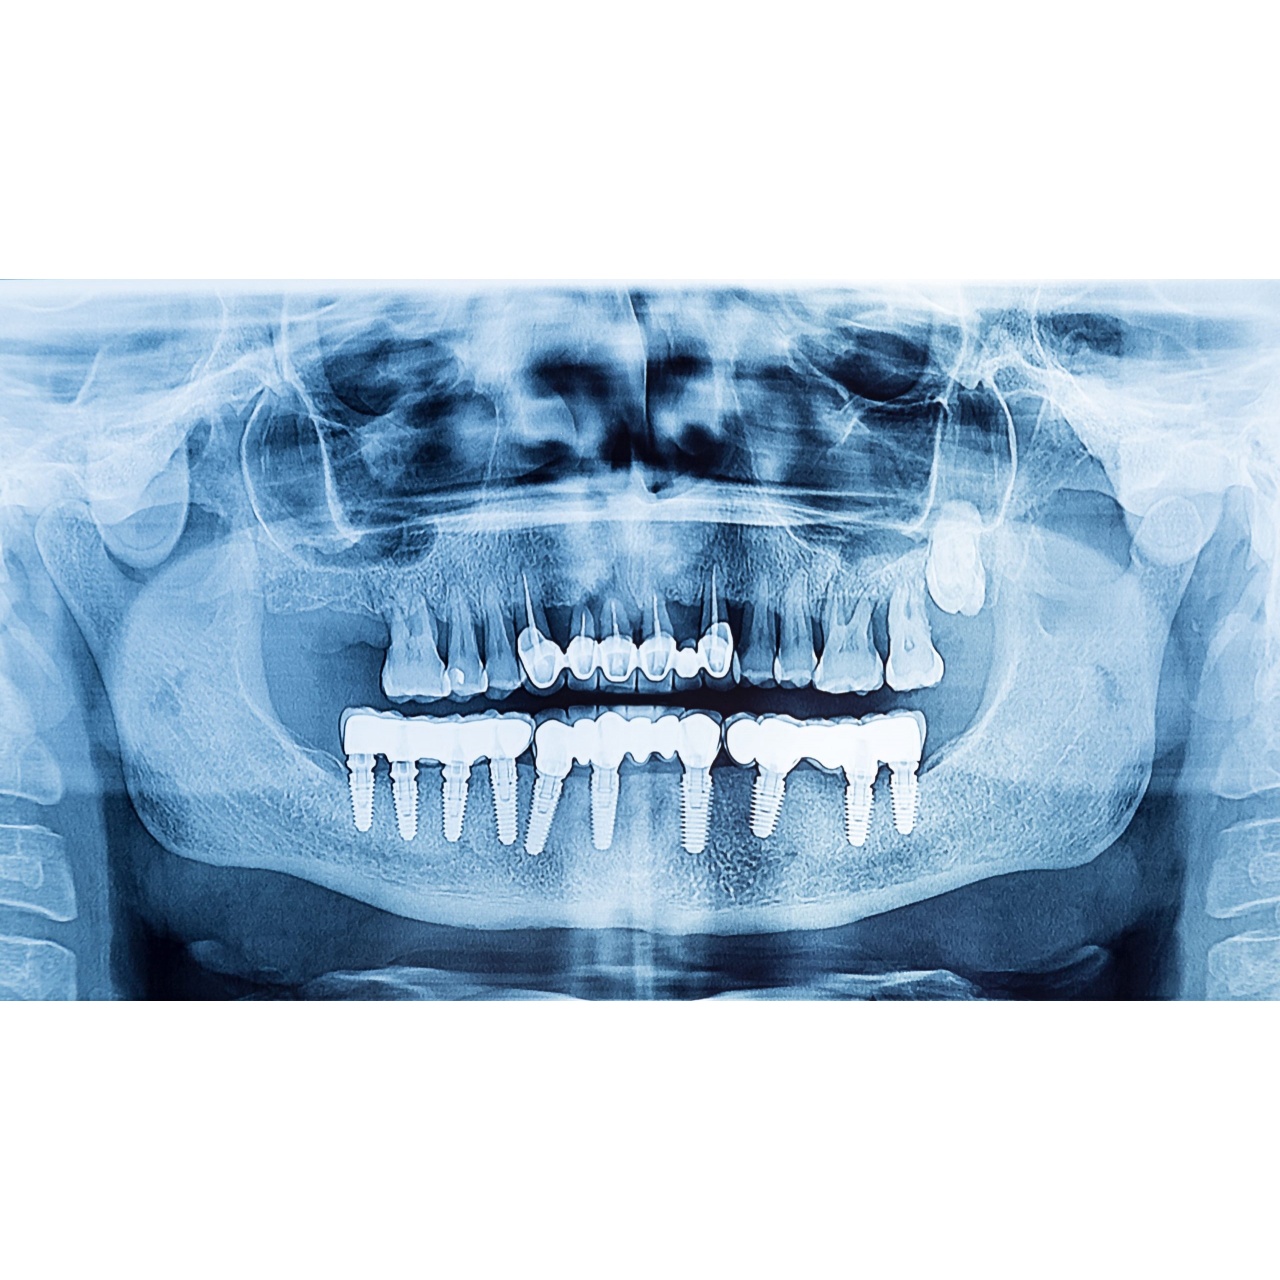

Dental Implants

When All Teeth are Lost